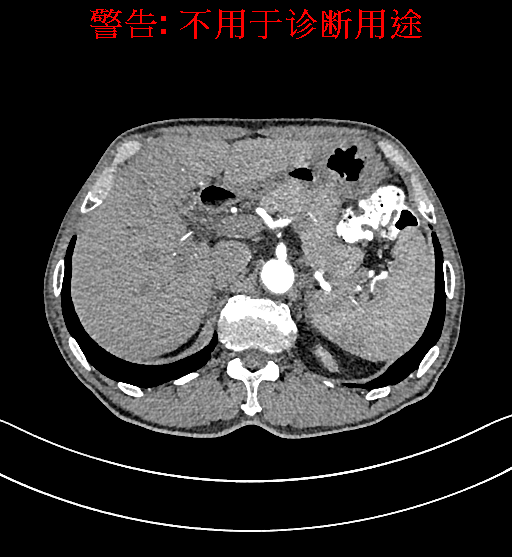

术前CT检查:

动脉期

静脉期

平衡期

上腹部动态CT扫描示肝左内叶占位,考虑肝Ca可能性大,请结合临床肝多发小囊肿。

通过调节窗宽窗位调整CT序号,对肿瘤,肝实质,胆囊,下腔静脉,肿瘤,肝动脉、门静脉及肝静脉等进行三维重建;系统自动计算肿瘤体积和肝脏体积。模拟手术操作,自动计算切除肿瘤体积。肝脏体积为1320ml,肿瘤体积为37.88ml,通过比对70-80岁正常肝脏体积为1263.13±170.25 ml,通过术前模拟手术,精准判断切除后剩余肝脏体积能耐受,避免肝衰竭发生。